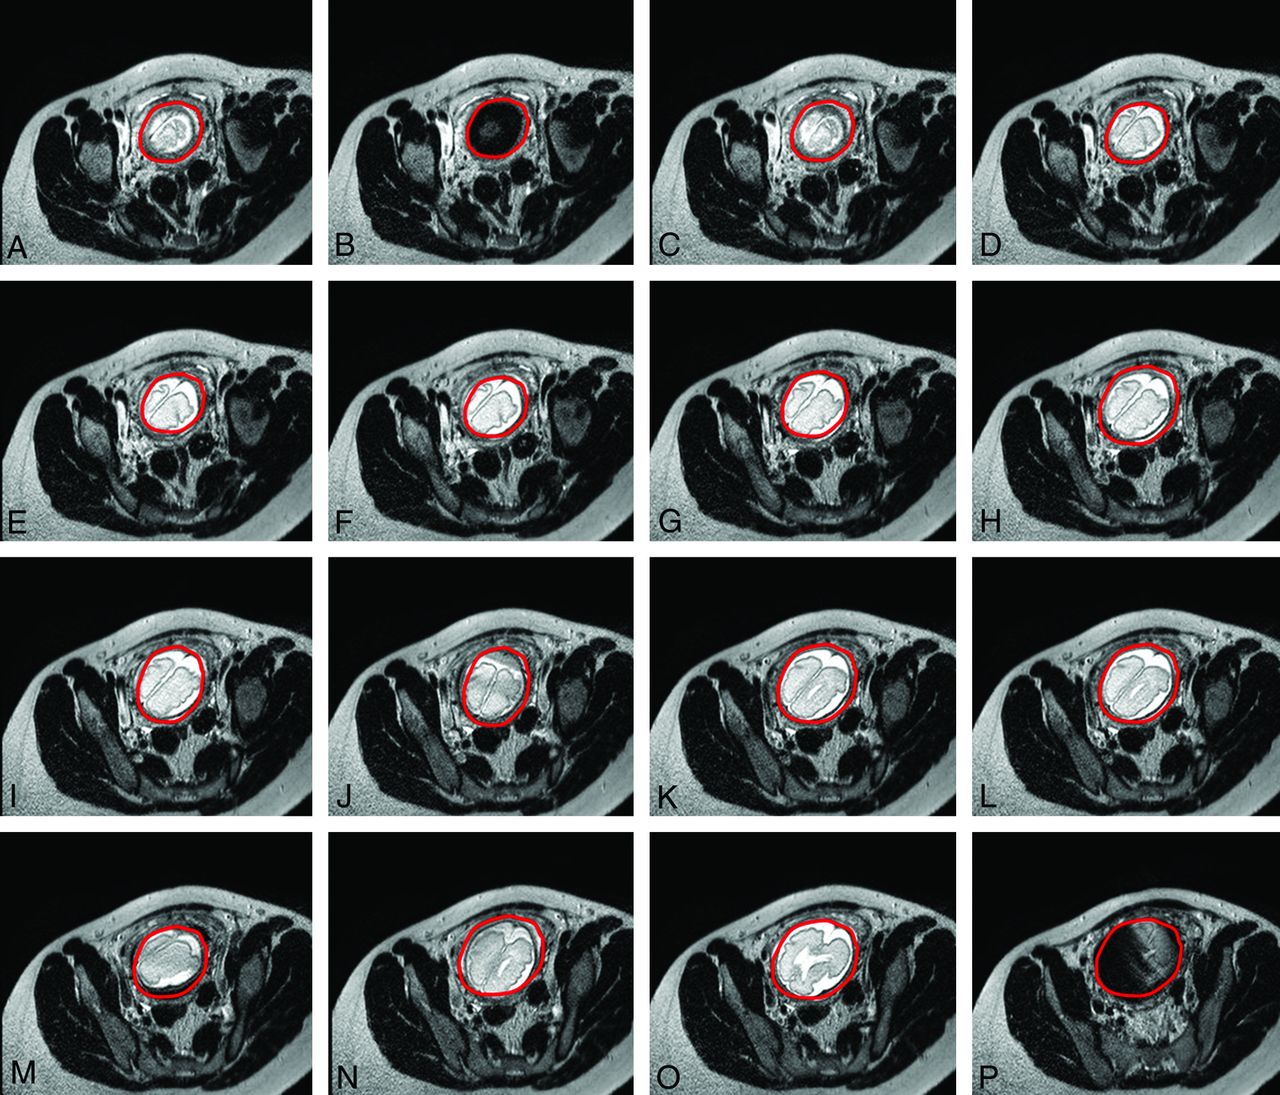

Motion artifacts may present as “blurring” (Fig 5C), “ghosting” (Fig 5J), contrast changes (Fig 5P), and even signal voids (Fig 5B) as described in the previous section. Blurring is similar to motion blur in photography, producing a marked decrease in spatial resolution; in the case of MR imaging though this is mostly evident in the phase-encoding direction, regardless of the actual direction of the original motion. Ghost images comprise lines concentric or parallel to bright imaged structures, such as subcutaneous fat on T1-weighted images, and represent full or partial replicas of the original static source. These should not be confused with the similarly appearing Gibbs ringing artifacts due to data truncation (Fig 6). Additionally, contrast changes and signal void may occur with very fast patient motion.

Successive axially planned sections of a single-shot fast-spin-echo acquisition at 1.5T (TR, 1000 ms; TE, 127 ms; section thickness, 4 mm; scanning duration, 26 seconds) of a 32-week-old fetus (E) with significant fetal motion occurring during data acquisition and resulting in blurring (C, J, M), contrast changes (P), and ultimately signal void when motion is extreme (B). Please note that though sections were planned in the axial plane, fetal movement resulted in plane transposition in the produced images (A–P) (fetal brain is circumscribed in red to distinguish it from neighboring maternal tissues).